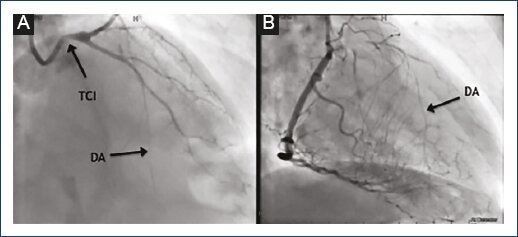

Se le realizó cateterismo cardíaco diagnóstico 24 h después de su ingreso a emergencia, el cual mostró oclusión severa del 95% en el ostium coronario izquierdo (Fig. 1) y resto de arterias coronarias sin lesiones angiográficamente significativas; además, se observó circulación colateral heterocoronaria de coronaria derecha a descendente anterior. Dos días después del cateterismo se realizó la cirugía de baipás coronario con el uso de arteria mamaria interna bilateral, colocándose la mamaria izquierda hacia arteria marginal y la derecha a descendente anterior.

Figura 1 A: coronariografía izquierda que muestra la lesión severa en el ostium del tronco izquierdo y adelgazamiento difuso de la DA. B: coronaria derecha sin obstrucciones y se evidencia la circulación colateral a la DA. CX: arteria circunfleja; DA: arteria descendente anterior; TCI: tronco coronario izquierdo.